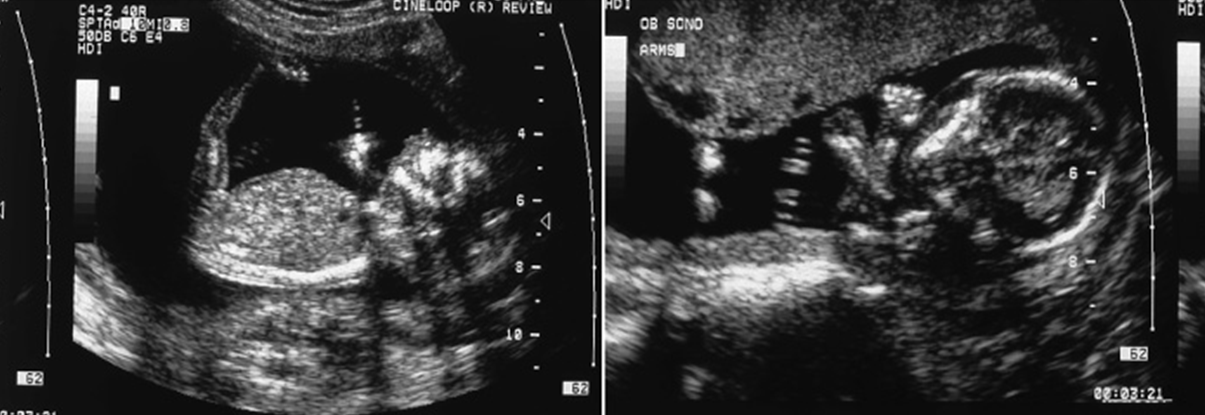

PUV Obstruction (Posterior Urethral Valve)